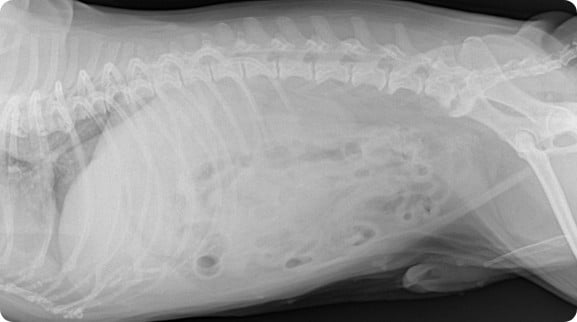

시그니처동물의료센터 『동물 종양 센터』에서는 림프종(lymphoma)과 같은 혈액암, 비만세포종(Mast cell tumor)을 비롯한 피부암부터 인슐린종(insulinoma)와 같은 희귀 내분비종까지 경험 많은 종양 의료진들이 각 환자에게 정확한 진단 및 적절한 치료를 이어나갈 수 있도록 노력하고 있습니다. 최소한의 마취로 CT 촬영을 통한 전이 평가, 외과적 절제술, 항암 치료까지 각 환자의 상태에 따라 최선의 치료를 이어갈 수 있도록 내외과 및 영상의학과의 의료진들이 협진하고 있습니다.